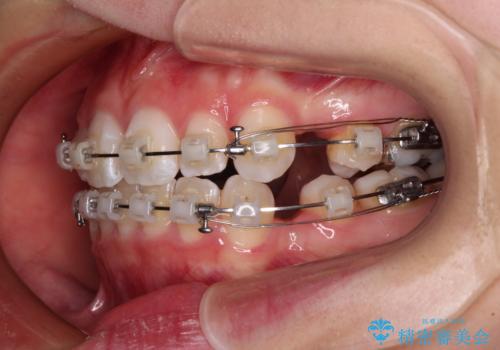

- クリアブラケット

- 1年6ヶ月

- 前歯の出っ歯と口元の閉じにくさを気にして来院された患者様です。

口元を積極的に引っ込めるために、上下左右の小臼歯4本を抜歯することとしました。

4本の歯を抜歯したことで、飛び出していた口元が引っ込み、横顔が大きく改善されました。